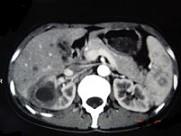

问题 女,33岁,右胁腹痛7天,尿检可见大量的脓细胞,CT平扫+增强如图所示,下列说法正确的是 ( )

选项 A.右肾体积增大,其内可见类圆形低密度病灶 B.增强扫描可见该病灶不均匀强化,其内有无强化的坏死灶 C.右肾病灶边界模糊不清 D.考虑为右肾囊肿合并感染 E.考虑为右肾脓肿

答案 ABCE